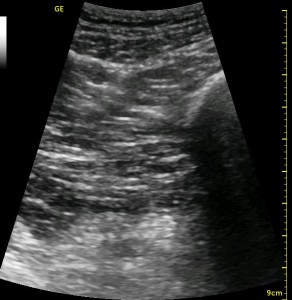

The following ultrasound image shows typical relationships of the sonoanatomy of the anterior sciatic nerve block. The femur is at 4cm on the right (lateral) of the image seen as a bright white horizontal line. Typically, there is a bone shadow below it, though there is some artifact below the femur here. The femoral vessels are seen between the 2cm and 3cm marks just to the right of center as a darkened area. They really can be determined by pausing for the appearance of arterial pulsation and venous compressibility. The adductors are seen to the left of the femur as a darkened area. Just deep to this between the 6cm and 7cm mark is a brightened rectangular shape, the sciatic nerve. The brightness fill fade with rocking of the probe over it. The nerve can be approached from the medial or lateral aspect of the probe, and moving the probe medially will sometimes allow for a better trajectory.

The image above is not an obvious one, and I did that on purpose. You have to get used to the idea that you will not always have a ‘super distinct’ image with this approach, and you will often need to use a number of additional clues to find your target and then to put local around it. I think the only way to really get a handle on being able to identify the basic elements is to look at several images over and over, so I have provided several below for you to use for practice. Note that the sciatic nerve will ‘poke out’ from behind the femur to different degrees depending on your orientation to the femur as well as to how far up or down the femur you go. It will be seen more if you are proximal. See how well you can identify the structures in the images below.